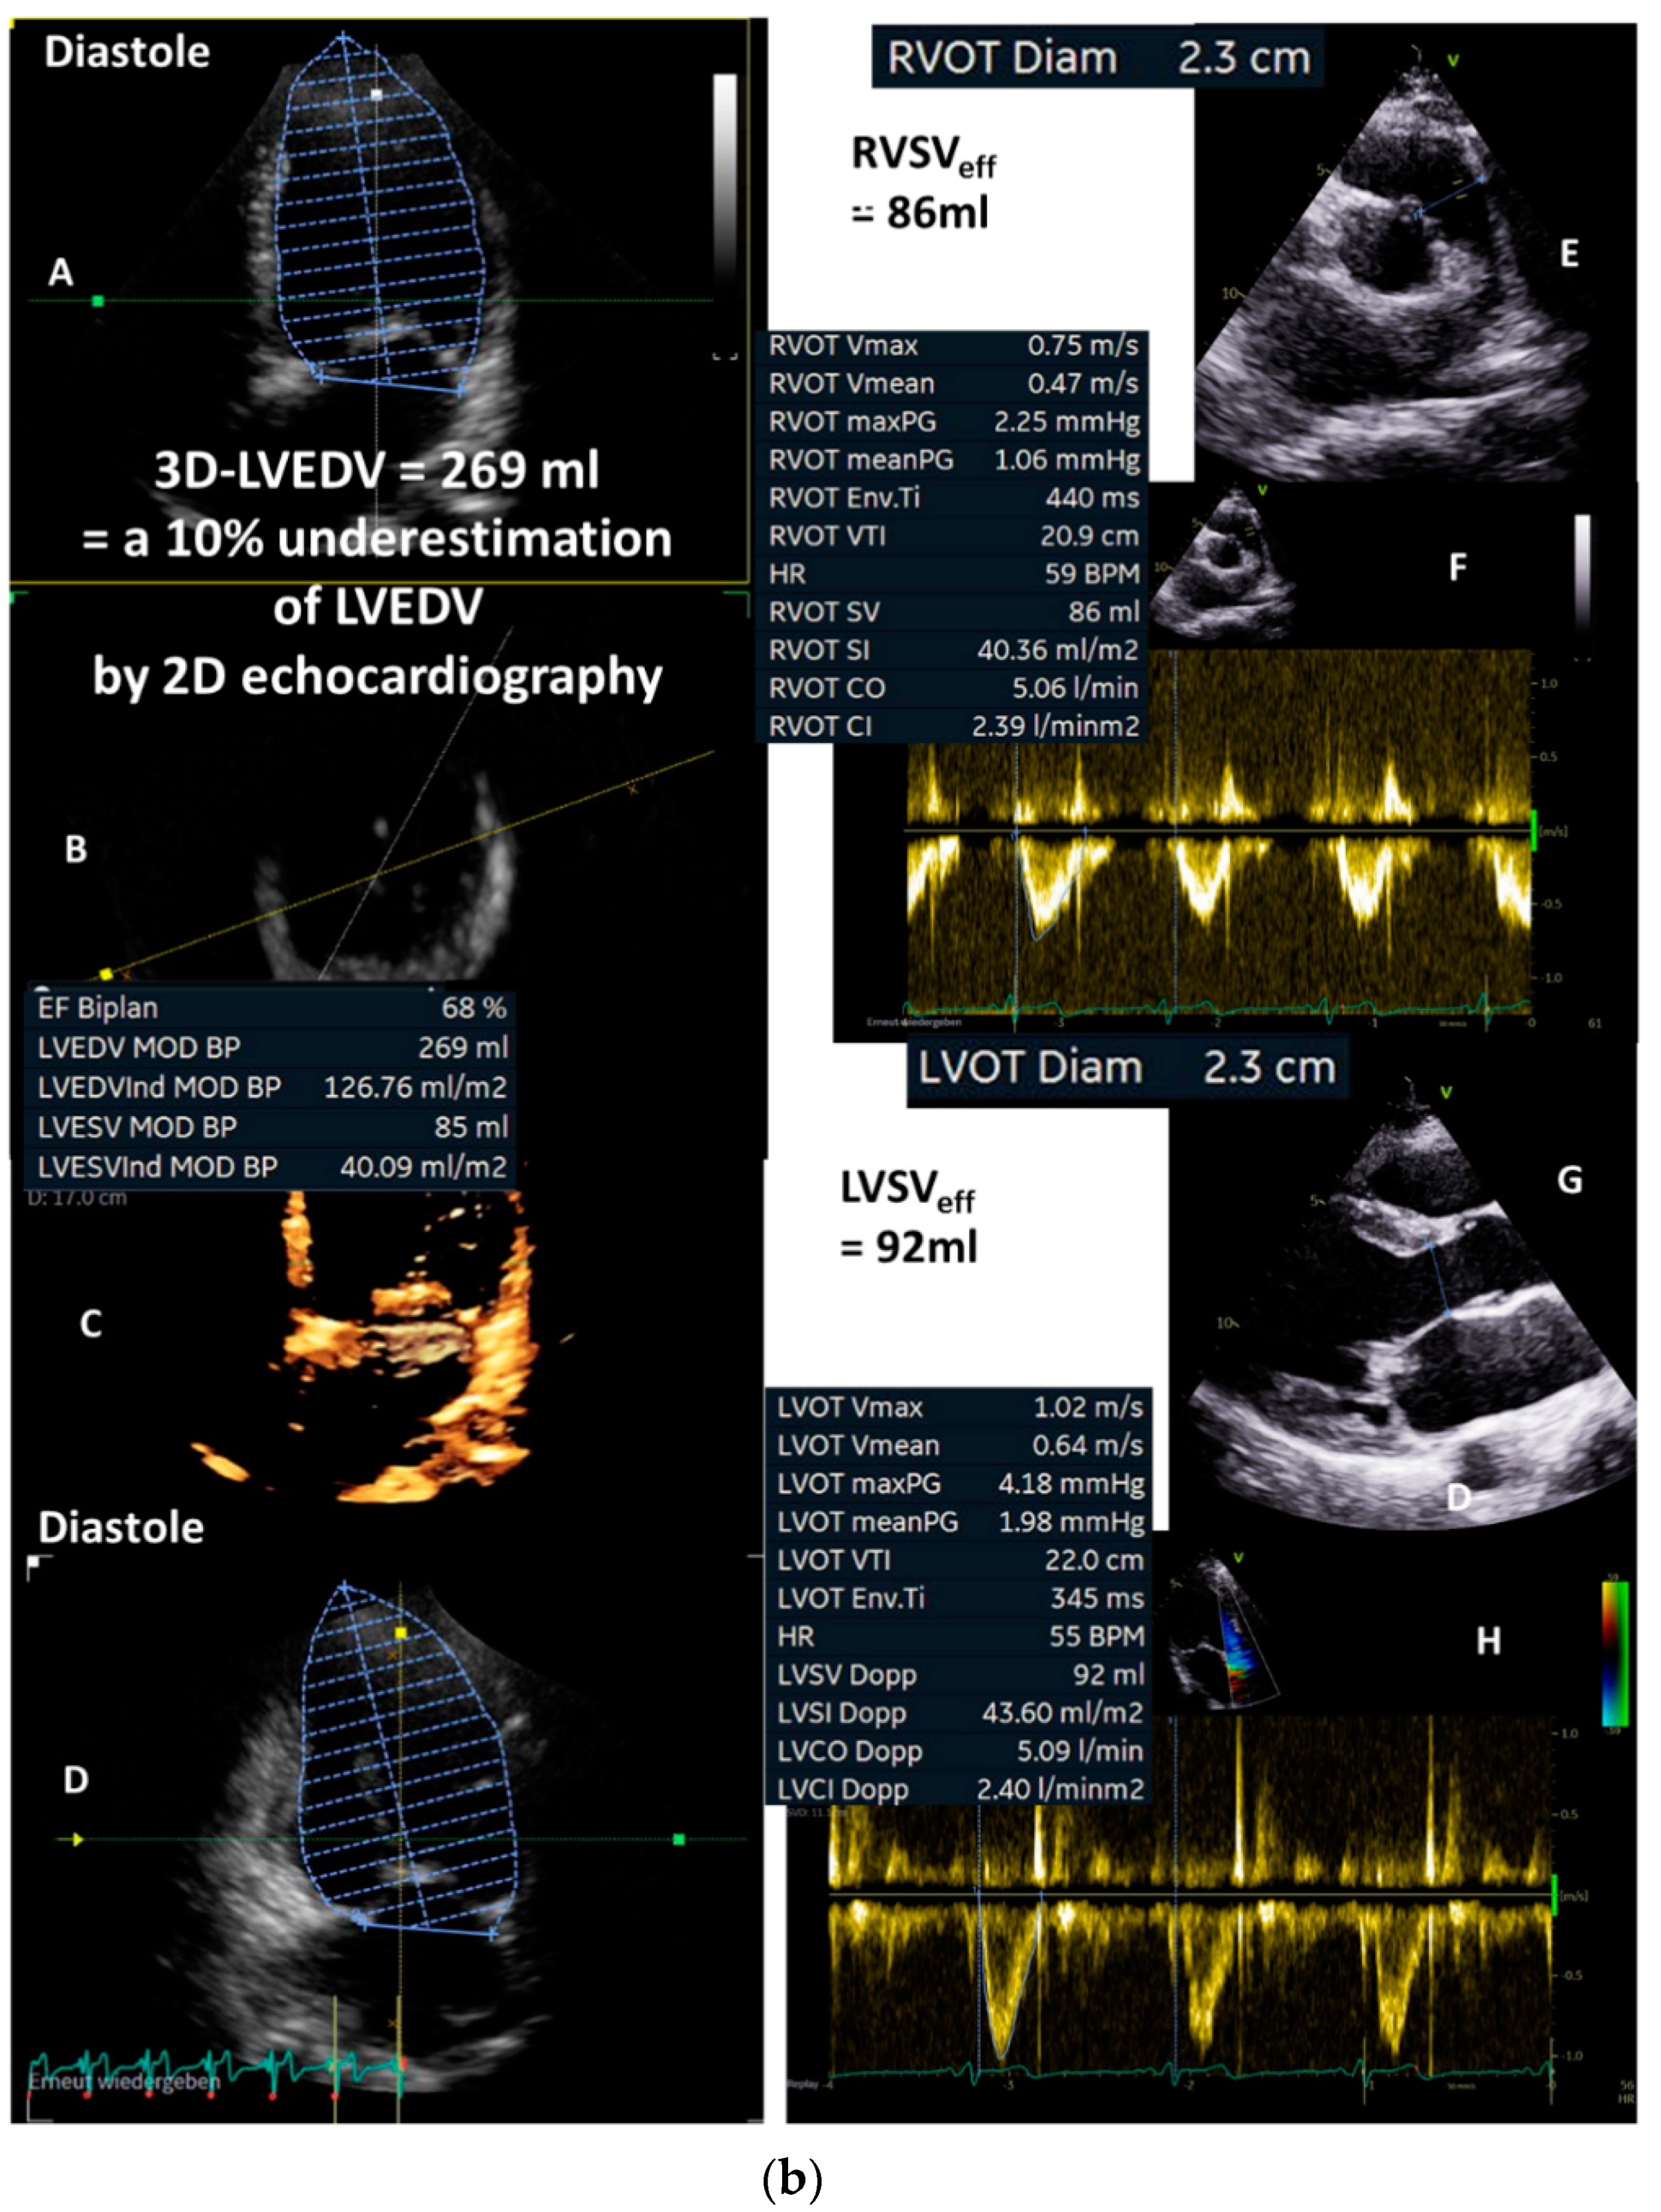

Figure 3.

(a): Illustration of underestimation of LVEDV and LVESV by 2D echocardiography: in (A), the planimetry of LVEDV in the two-chamber view (2-ChV) is shown; in (B), the corresponding LVESV is shown. In (C), the planimetry of LVEDV in the four-chamber view (4-ChV) is shown; in (D), the corresponding LVESV is shown. However, the obvious difference between the longitudinal LV axis in the 4-ChV between diastole and systole indicates the foreshortening of the 4-ChV causing errors of LV volume assessment. LVSV = left ventricular stroke volume, LVSVtot = total LVSV, LVSVeff = effective LVSV, LVEDV = left ventricular end diastolic volume, and LVESV = left ventricular end systolic volume. (b): Measurements of the corresponding LVEDV areas in adjusted sectional planes by postprocessing in a 3D dataset in comparison with the 2D echocardiography presented in (a): in (A), the LVEDV assessment of the adjusted four-chamber view is shown; in (B), the perpendicular lines of the apical planes in the short-axis view of the 3D dataset are shown; in (C), the 3D view of the azimuth plane is shown; in (D), the LVEDV assessment of the adjusted two-chamber view is shown. In (E), a parasternal short-axis view during systole to label the RVOT is shown. In (F), the RVOT-pw-Doppler spectrum is shown. In (G), a parasternal long-axis view during systole to label the LVOT is shown. In (H), the LVOT-pw-Doppler spectrum is shown. Estimation of effective LVSV is performed with pw Doppler echocardiography by determination of forward RVSV. In isolated mitral regurgitation, a countercheck can be performed by assessment of forward LVSV which corresponds to forward RVSV. LVSV = left ventricular stroke volume, RVSV = right ventricular stroke volume, LVSVtot = total LVSV, LVSVeff = effective LVSV, LVEDV = left ventricular end-diastolic volume, RVOT = right ventricular outflow tract, and LVOT = left ventricular outflow tract.